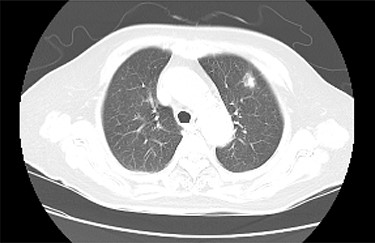

Chest CT detected a nodule with an irregular margin measuring 17 × 14 mm in size at the subpleural area of the left upper lobe S3 of the lung.

A 80-year- Japanese woman first visited our hospital in March 2017 with several neurological symptoms such as headache, incontinence, wobble and consciousness disorder (Glasgow Coma Scale: 14). She was a smoker (from 18 to 80 years of age, one pack per day, Brinkman Index: 1240) and had no family history of malignancies. Brain magnetic resonance imaging (MRI) revealed hyperintense signals on T2-weighted (Fig. 1A) and fluid attenuation inversion recovery (FLAIR) images at the splenium of the corpus callosum (Fig. 1B). These findings were compatible with limbic encephalitis. A cerebrospinal fluid analysis showed inflammation with negative cytology, and an electroencephalogram demonstrated normal study. Because PLE due to malignant tumor was suspected, a systemic examination was performed. Chest computed tomography (CT) detected a nodule with an irregular margin measuring 17 × 14 mm in size at the subpleural area of the left upper lobe S3 of the lung (Fig. 2). The enhanced systemic CT and brain MRI detected neither regional lymph node swelling nor distant metastases, and then it was classified as clinical stage T1bN0M0 according to the eighth edition of the TNM classification by International Association for the Study of Lung Cancer (IASLC). Her conscious level was worsening (Glasgow Coma Scale: 5). After obtaining informed consent, lung partial resection was performed via video-assisted thoracic surgery (VATS). The permanent pathological examination revealed squamous cell carcinoma (keratinizing type) (Fig. 3), and it was classified as pathological stage T1bN0M0. Anti-Hu antibody, one of onconeural antibodies, was investigated as part of the workup for PLE, but the result was negative. Her post-operative course was uneventful, but she died 50 days after surgery caused by the rapid progression of encephalitis.